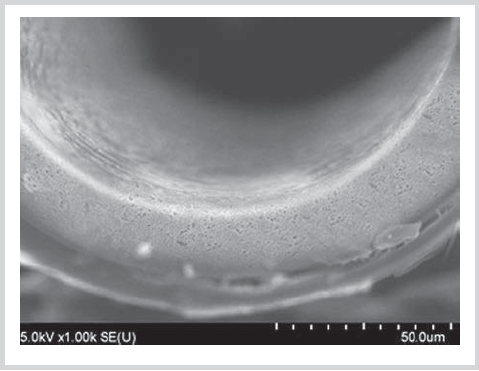

Primary microscopic evaluation. Original coated membrane samples dried under vacuum were examined by electron microscopy to collect control data. A 20—25 nm thick tungsten layer was sprayed on samples using a Cressington 208HR sputter coater. Microphotographs were acquired with a Nova NanoSEM scanning electron microscope (FEI, USA).

Primary microscopic evaluation (Fig. 2—4)

Fig. 4. A cross-section of a coated sample A (×1,000).

Primary microscopic evaluation demonstrated that a 10 μm thick stable defect-free coating formed on samples.